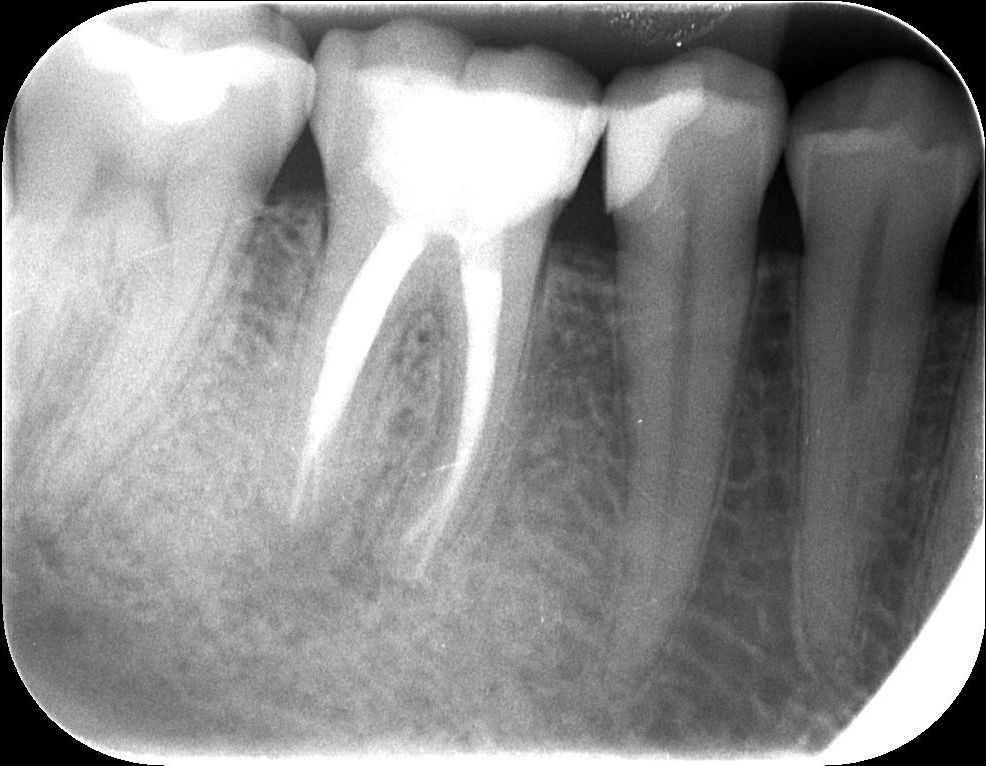

A régi gyökértömés eltávolítása, illetve a csatornák teljes feltárása után a későbbi gyökértömő „pálcikákkal” készült röntgenfelvétel. Ezen ellenőrizzük le a gyökértömés készítése előtt, hogy valóban jól dolgoztunk-e, és hogy sikerült-e minden csatornának eljutni a végéig.

mikroszkópos gyökérkezelés 2. kép